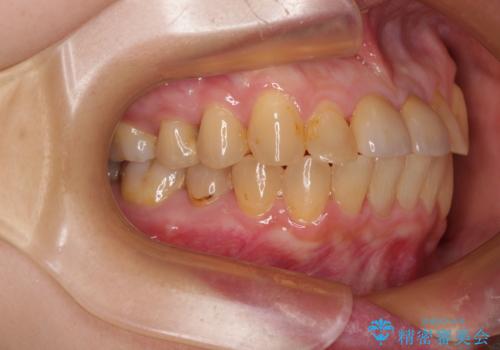

前歯のデコボコをワイヤー矯正できれいに整える

- 前歯のデコボコと変色した前歯を気にして来院された患者様です。

抜歯矯正により口元を引っ込めることも検討しましたが、特に口元の突出感は気になっていないとのことで、非抜歯にてワイヤー装置で矯正治療を行うこととしました。

気になっていた前歯の変色も、矯正治療後にオールセラミッククラウンにて補綴治療を行うこととしました。

舌の突出癖により治療期間中に開咬となり、治療が長引きましたが、口元も治療前よりも引っ込めることができ、すっきりとした仕上がりとなりました。